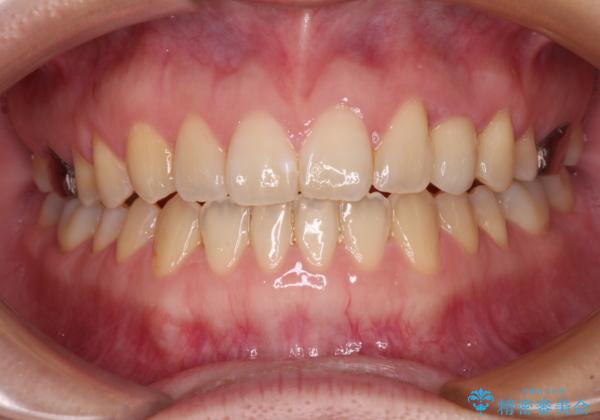

- 前歯の開咬と、受け口による咬み合わせの悪さを気にして来院された患者様です。

矯正治療が終わるタイミングに合わせてインプラントの埋入を行っていたので、矯正治療を終了すると同時にセラミック補綴治療を行えました。

インビザラインの装着時間が不十分であったので、治療期間は長期間となりました。